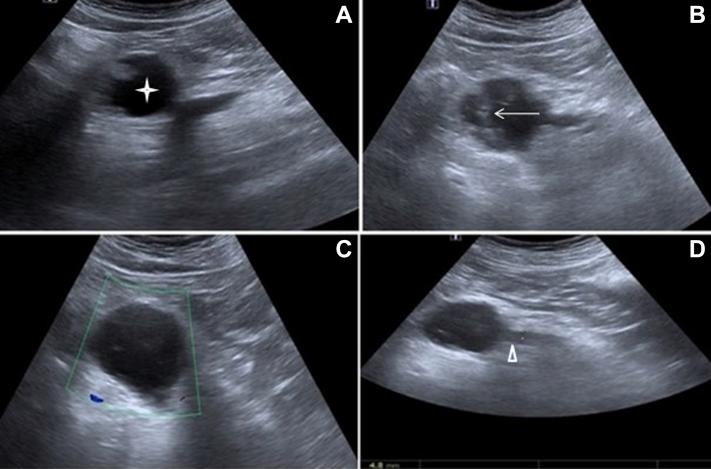

Intraductal papillary mucinous neoplasia (IPMN) is one of the cystic neoplasias of the pancreas. The imaging findings provide that these tumors are differentiated from the other cystic lesions of the pancreas, especially from the chronic pancreatitis, where the treatment protocol is completely different. Therefore, the correct diagnosis and classification of the IPMN ensures that the patient receives the correct approach and the appropriate surgery, if necessary. The purpose of this study is to emphasize the imaging findings of the different types of the IPMN and the changes in the management protocol of the patients according to these radiological findings.